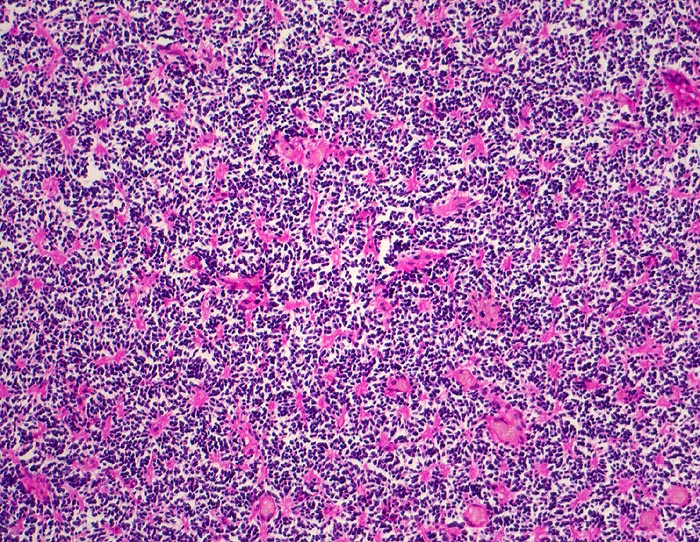

Wegen der hohen Zelldichte und der hohen Kern-Zytoplasmarelation erscheinen die Tumoren in der HE Färbung blau. Medulloblastome müssen differentialdiagnostisch von morphologisch ähnlichen kleinzelligen undifferenzierten Karzinomen und Lymphomen abgegrenzt werden. Das klassische Medulloblastom besteht aus dicht gepackten Zellen mit runden bis ovalen oder karottenförmigen stark hyperchromatischen Kernen umgeben von wenig Zytoplasma. Runde Zellen mit weniger dichtem Chromatin sind oft beigemischt. Zahlreiche Mitosen, flächenhafte Nekrosen und Apoptosen sind typisch. In weniger als einem Drittel der Fälle findet man die typischen Homer-Wright Rosetten. Diese bestehen aus ringförmig angeordneten Tumorzellkernen um ein fibrilläres Zentrum aus Zytoplasmafortsätzen.

• Scharf begrenzter rundlicher sehr zellreicher (deshalb blauer) Tumor.

• Monomorpher Zellrasen mit hyperchromatischen ovalen oder karottenförmigen Zellkernen.

• Kaum erkennbares Zytoplasma.